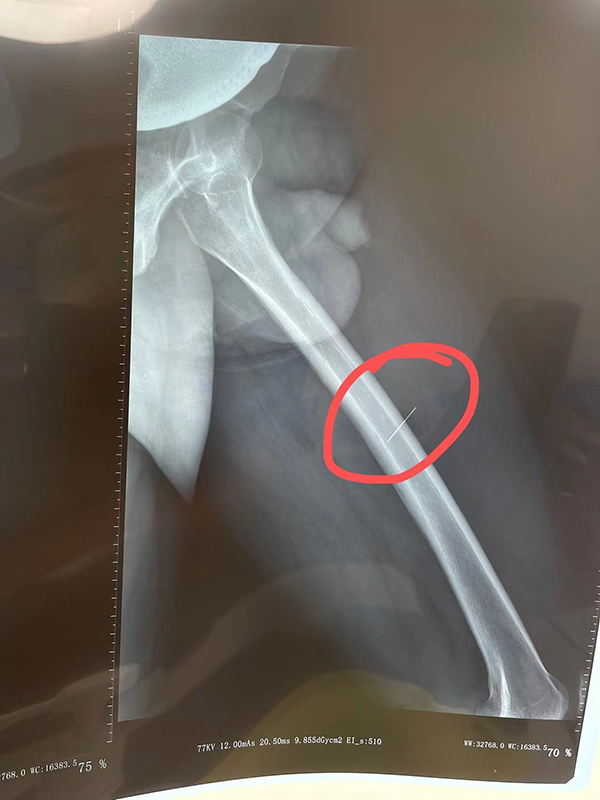

10月6日傍晚时分,应急总医院急诊科来了一位男性患者,主诉左侧大腿射进了一枚钉子,还留在体内。

骨一科值班医生王新光接到急诊科的紧急会诊通知后,火速赶到急诊清创室。经过了解,这位患者是一名建筑工人,在施工作业时不慎将一枚钉子射入左大腿内侧。

根据X线片定位,骨一科医疗组二线医生邵楠紧急从家里赶到医院展开术前讨论,制订治疗方案。

钉子射入大腿内侧

钉子扎在大腿内侧较深的位置,靠近股动脉和隐神经,必须尽快通过手术取出,否则钉子就留在了体内,可能引起感染化脓、甚至移位扎破血管或损伤神经,可是根据以往的经验,这样的手术需要在手术室做硬膜外麻醉,在创口处切开一个较大切口探查,而且钉子隐藏在血液、体液及软组织中,找起来非常困难。这时候大家想到了平时常用的肌骨超声技术,能否依靠肌骨超声仪定位钉子的位置,仅仅在局部麻醉下伸进去一把血管钳把钉子夹取出来。